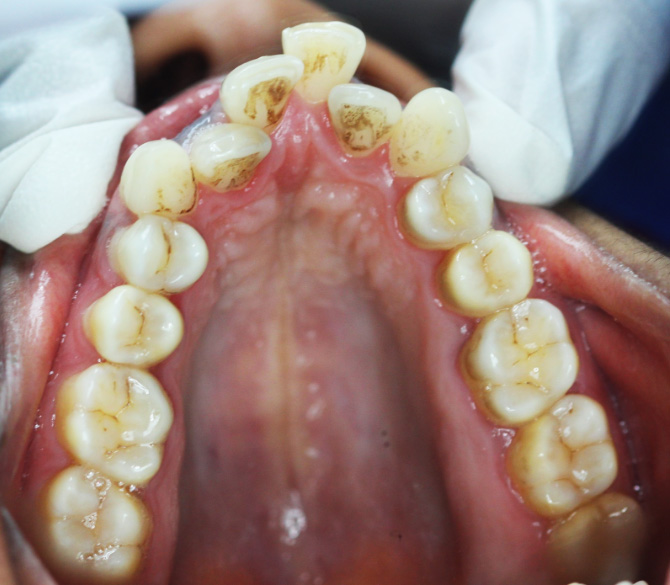

Before Treatment (Initial Assessment)

An initial assessment was carried out to understand the patient’s dental alignment and presenting complaints.

Intraoral Images: — (Before-treatment images)

The patient was diagnosed with Angle’s Class I malocclusion, along with crowded teeth and a crossbite. These conditions caused improper alignment of the teeth and an uneven bite.